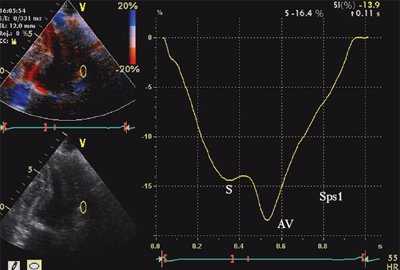

На рис. 3-5 приведены различные варианты ПСУ у больных с постинфарктным кардиосклерозом.

![Тканевая допплерография в норме. У больного с постинфарктным кардиосклерозом регистрируется высокоамплитудный пик постсистолической скорости (Sps)]()

![Тканевая допплерография при постинфарктном кардиосклерозе. У больного с постинфарктным кардиосклерозом регистрируется высокоамплитудный пик постсистолической скорости (Sps)]()

б) При постинфарктном кардиосклерозе. У больного с регистрируется высокоамплитудный пик постсистолической скорости (Sps).

Вертикальная линия (AV) на рис. 3-5 соответствует времени закрытия аортального клапана. На представленных графиках также отмечается наличие базально-верхушечного градиента (снижение пиковых миокардиальных скоростей, продольного систолического смещения и деформации от основания к верхушке левого желудочка).